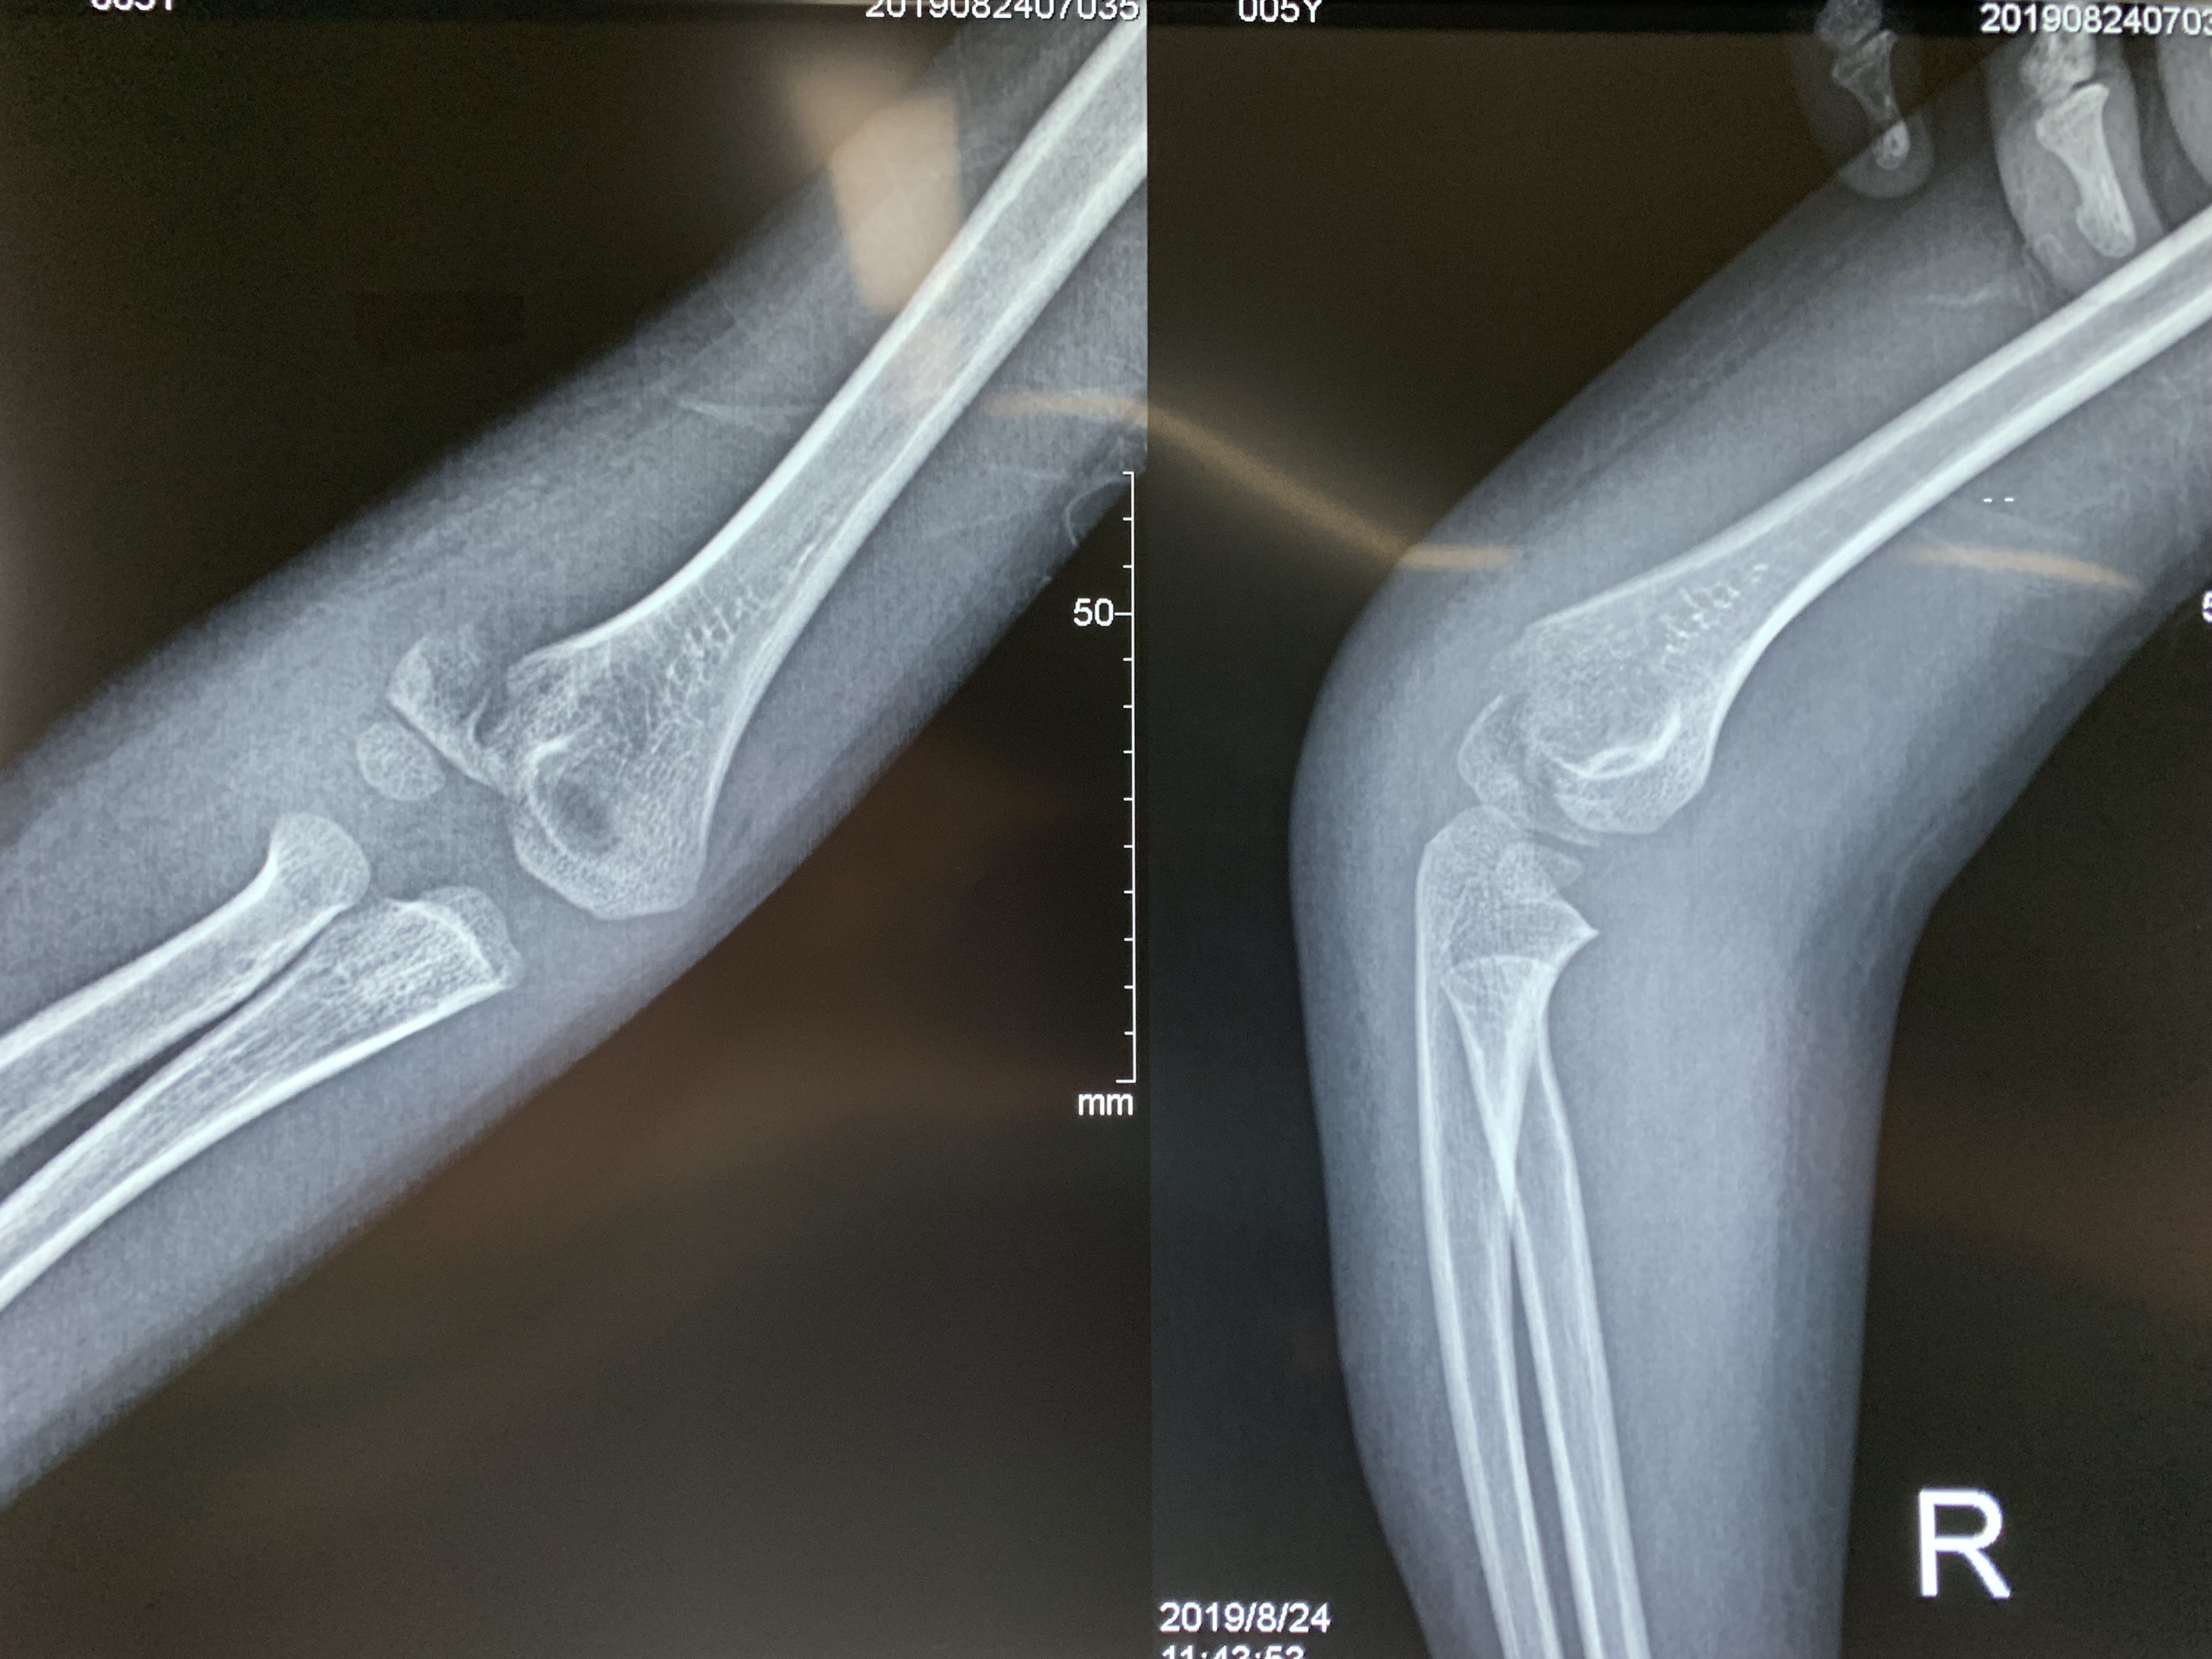

肱骨外髁骨折程度[s0]肱骨外髁骨折分型[s1]肱骨外髁骨折的临床表现[s2]肱骨外髁骨折Ⅲ型复位手法[s3]肱骨外髁骨折,保守治疗可以吗[s4]小儿肱骨外髁骨折[s5]儿童肱骨外髁骨折,医生不说你很可能永远都不会知道的[s6]不同类型的肱骨外髁骨折[s7]肱骨外髁骨折概述[s8]六、肱骨外髁骨折 - 图1[s9]六、肱骨外髁骨折 - 图2[s10]图片[s11]肱骨外髁骨折 m.haodf.com[s12]图片[s13]肱骨外髁骨折[s14]img[s15]肱骨外髁骨折.[s16]分期矫正儿童肱骨外髁骨折不愈合伴肘外翻畸形[s17]肱骨外髁骨折[s18]肱骨外髁骨折翻转90°,复位后克氏针或螺钉固定(自ao)[s19]右肱骨外髁骨折切开复位内固定术[s20]img[s21]img[s22]赵景新's media[s23]一例儿童右肱骨外髁骨折病例[s24]肱骨外髁骨折,保守治疗可以吗[s25]小儿肱骨外髁骨折[s26]肱骨外髁骨折固定[s27]肱骨外髁骨折 www.iiyi.com[s28]小儿肱骨外髁骨折的诊断和治疗[s29]右肱骨内外髁骨折[s30]图36-48 肱骨外髁骨折的不同程度移位 a型无移位;b型中度移位;c型完全移位伴旋转[s31]肱骨外髁骨折 www.haodf.com[s32]肱骨外髁骨折 www.haodf.com[s33]问:左肱骨外髁骨折,左肘关节脱位,6.[s34]儿童肱骨外髁骨折 - 小红书[s35]儿童肘关节损伤之--肱骨外髁骨折[s36]▲右侧肱骨外髁骨折闭合复位克氏针固定及石膏固定术后。“幸亏在掉落的[s37]肱骨外髁骨折 www.guahao.com[s38]肱骨头及外髁骨折,求诊治方案,手术还是非手术[s39]